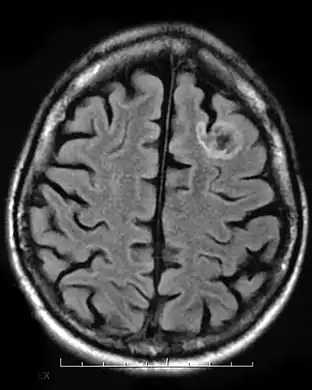

Dysembryoplastic neuroepithelial tumour, MRI FLAIR.

A dysembryoplastic neuroepithelial tumour is commonly diagnosed in patients who are experiencing seizures with magnetic resonance imaging (MRI), electroencephalogram (EEG).[4] A DNT is most commonly diagnosed in children who are experiencing seizures, and when given medication do not respond to them. When an MRI is taken there are lesions located in the temporal parietal region of the brain.[4]